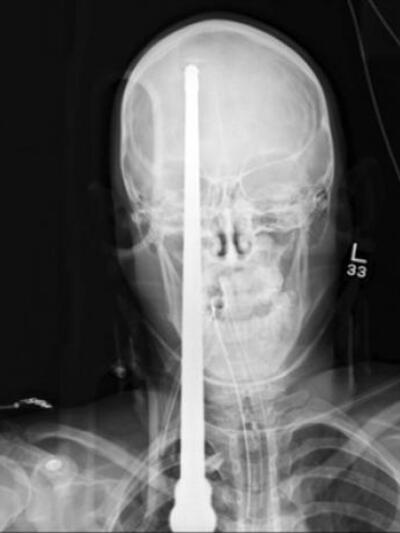

Μέχρι και η... επέμβαση της Πυροσβεστικής Αγρινίου χρειάστηκε σήμερα, ώστε να κόψει τη βέργα ψαροντούφεκο που από το λαιμό τραυματία στο Αγρίνιο, βγήκε από το πάνω μέρος του κρανίου του!

Οι συνθήκες του τραυματισμού του άνδρα δεν έχουν ακόμη αποσαφηνιστεί, αλλά το χτύπημα από την βέργα του ψαροντούφεκου που δέχτηκε ο 42χρονος ήταν τέτοιο που από το λαιμό του, διαπέρασε τον εγκέφαλο και η μύτη της βέργας βγήκε από το πάνω μέρος του κρανίου.

Ο άνδρας μεταφέρθηκε αμέσως στο νοσοκομείο του Αγρινίου και άφωνοι έμειναν γιατροί και νοσηλευτές μόλις αντίκρισαν το θέαμα. Ανάλογος τραυματισμός έχει σημειωθεί ένας ακόμη στην Ελλάδα και συγκεκριμένα στην Κρήτη σύμφωνα με πληροφορίες.

Αμέσως κλήθηκε η Πυροσβεστική, σύμφωνα με πληροφορίες του agriniopress.gr, για να κόψει τμήματα της βέργας και στη συνέχεια ο νευροχειρούργος του νοσοκομείου, κατάφερε να βγάλει τη βέργα από το πάνω μέρος του κρανίου του τραυματία. Στη συνέχεια ακολούθησε επέμβαση ώστε να αντιμετωπιστούν τα τραύματα και ο 42χρονος νοσηλεύεται στην Μονάδα Εντατικής Θεραπείας του Αγρινίου.